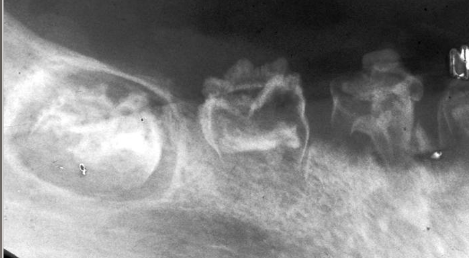

nonhereditary developmental anomaly, most common in max ant teeth, usually involves one quadrant, very large pulps with minimal dentin and enamel

regional odontodysplasia “ghost teeth”